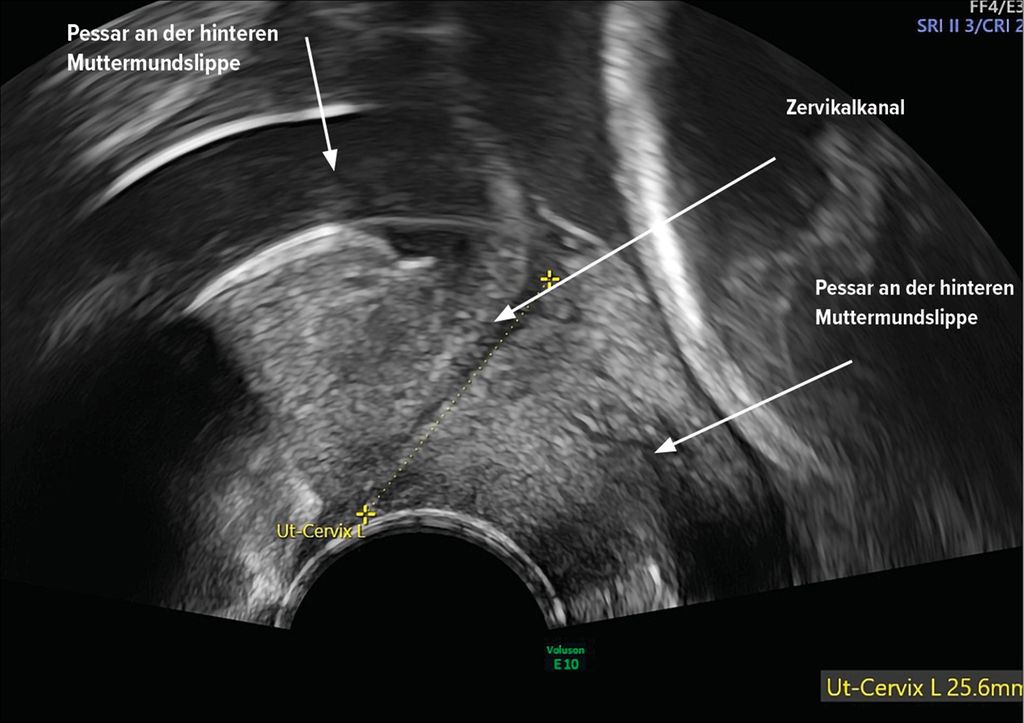

Cerclage

Eine mechanische Entlastung kann das Risiko für Frühgeburt reduzieren, indem Druck und Zugkräfte auf die Zervix verringert werden. Die Cerclage ist im Vergleich zum Zervixpessar ein operatives Verfahren, dasdurch eine Bandeinnaht zu einer mechanischen Verstärkung des Zervixgewebes führt und damit zur Verhinderung einer Öffnung und Verkürzung des Gebärmutterhalses führen kann (Abb. 4). Es wird nur auf die Cerclageindikationen bei asymptomatischen Schwangeren eingegangen, nicht auf die Notfallcerclage bei prolabierender Fruchtblase. Die Arbeiten beziehen sich auf die Cerclage nach Shirodkar oder McDonald.